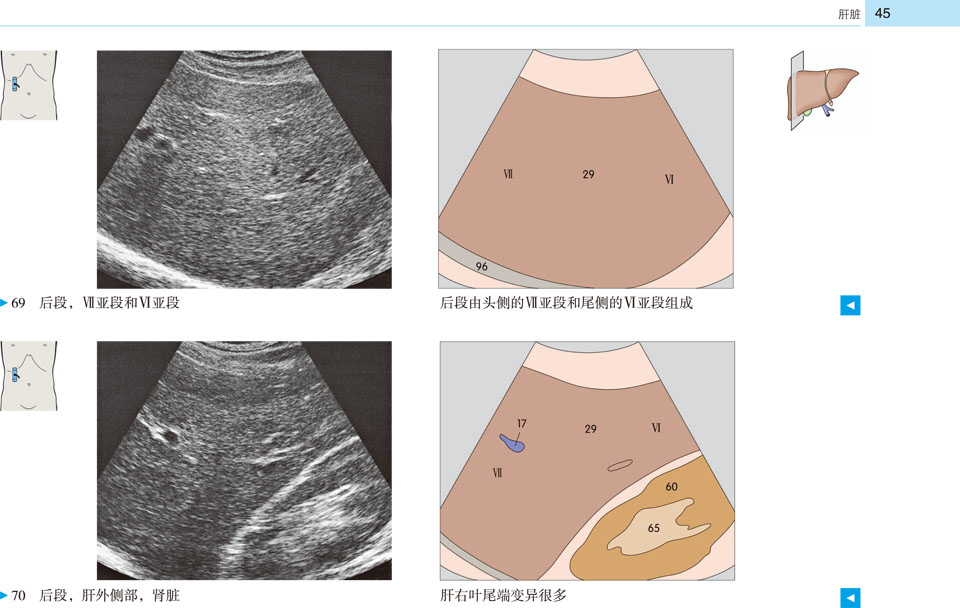

本书提供了全新的、高质量的超声图像和示意图,标示清晰、色彩丰富,为初学者带来极大的帮助。展示了腹部、盆部、甲状腺超声的所有标准切面和扫描路径,标示了各解剖结构和间隙在三维空间的解剖细节及其与超声的关系;并展示了探头定位,以及生成的截面图像、解剖结构、扫描平面在器官中的位置。本书作为优秀的初学者向导,适用于医学生、超声科医师、临床各科医师。